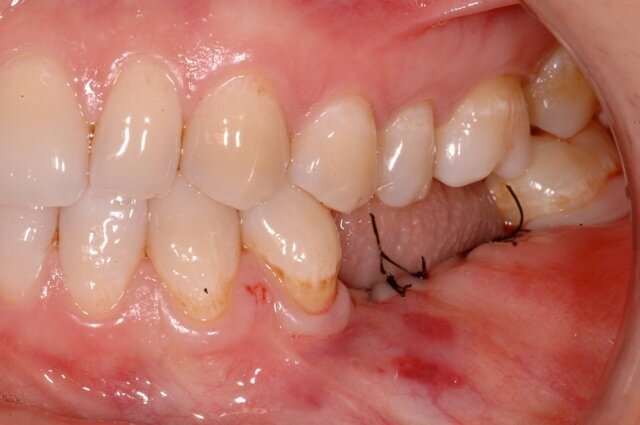

La passivazione del lembo è un aspetto molto importante di questa procedura perché deve garantire da una parte la perfetta chiusura e sigillo al di sopra della lamina, dall’altra mantenere una leggerissima tensione tale da mantenere la lamina ferma nella posizione in cui è stata stabilizzata all’anatomia locale. Il protocollo prevede di suturare inizialmente le due papille mesiali e distali con un doppio punto, e poi, una volta stabilizzati gli estremi ci si cura di ancorare la parte centrale della lamina con una sutura da materassaio orizzontale che ha una doppia funzione: stabilizzare la lamina schiacciandola e facendola aderire intimamente con la cresta e l’innesto sottostante, e nel contempo riposizionare i due lembi in senso coronale. Questo faciliterà poi la chiusura finale dei tessuti nella porzione crestale, che potrà avvenire, a seconda del caso con semplici punti staccati oppure con una sutura continua bloccante (Fig. 10). Nelle figure 11 e 12 si può ben osservare la dislocazione tridimensionale dei tessuti e le variazioni volumetriche prima e dopo l’intervento.

A sei mesi dall’intervento chirurgico la paziente venne sottoposta ad una nuova CBCT di controllo e questa evidenziò come i volumi stavano cambiando e l’osso innestato si stava mineralizzando al di sotto della lamina corticale, in bianco si nota la variazione volumetrica rispetto a quella che era la condizione iniziale (in blu) (Fig. 13). A dodici mesi dal primo intervento si decise di intervenire per inserire nella zona due impianti come da progetto iniziale, dopo aver anestetizzato la paziente con Articaina 1:200.000 una nuova incisione a mezza cresta permettè di scostare i lembi vestibolari e linguali per esporre la nuova cresta ossea ora con uno spessore di 8 mm nella parte posteriore e 6 mm nella porzione più anteriore. Questo consentì il posizionamento di due impianti a vite Bredent uno di diametro 4.5 x 8,5 mm di lunghezza (nel sito del molare) e uno di diametro 4 x 8,5 mm di lunghezza nel sito del secondo premolare13 (Figg. 14, 15).

Nella rx si vedono i due impianti con le viti di guarigione ad integrazione avvenuta. In figura 16 si nota l’ottimo aspetto dei tessuti peri-implantari con una adeguata quantità e qualità di gengiva cheratinizzata e le susseguenti corone in metallo ceramica successivamente cementate su due perni moncone in titanio fresati in laboratorio. Nelle foto successive si possono evidenziare le differenze dalla situazione iniziale (Fig. 17) a quella finale, in questo caso una foto di follow up a 48 mesi dalla finalizzazione del caso (Fig. 18). La rx a quattro anni dalla finalizzazione protesica evidenzia una situazione di perfetta stabilità, una cresta ossea ben mineralizzata ed un livello osseo inalterato dal momento della consegna del manufatto protesico definitivo (Fig. 19).